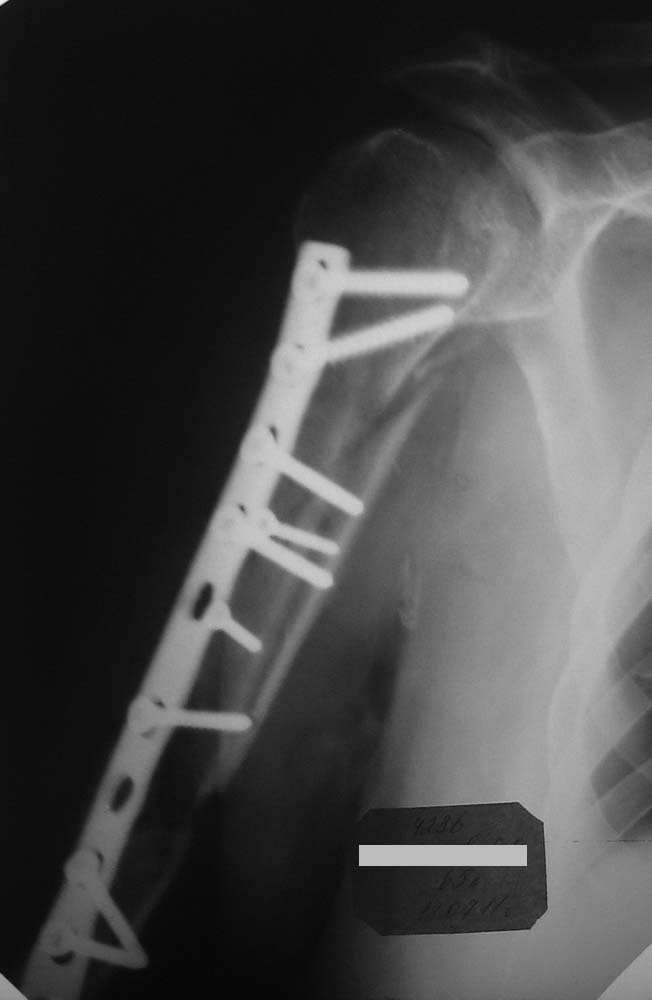

Последний R-снимок - со стержневым аппаратом.

Штифтами для интрамедуллярного синтеза не было, поэтому синтезировали тем, что было (пластина на 11 отверстий).

Снимки, к сожалению, оставляют желать лучшего.

Но то, что я вижу нельзя отнести к стабильному остеосинтезу.Раз уж Вы открылись "по полной" то важно хорошо репонировать отломки и зафиксировать винтами через оба кортикала. Возможно были интраоперационные проблемы,которые как-то помешали это сделать.Понять и осмыслить свои ошибки - это путь к их предотвращению в дальнейшем, ведь от этого никто не застрахован :)